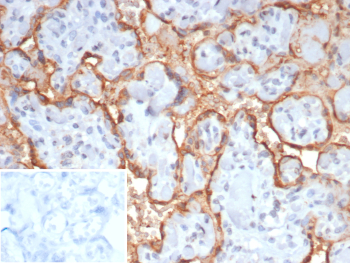

Immunohistochemistry analysis of formalin-fixed, paraffin-embedded human placenta tissue using CGB3 antibody (clone HCGb/7512R). Prominent membranous and pericellular staining is observed in trophoblastic cells, with signal outlining villous structures and minimal background staining in surrounding stromal areas. Nuclei are counterstained in blue. Inset shows PBS substituted for the primary antibody as a secondary-only negative control. Heat-induced antigen retrieval was performed by heating tissue sections in 10 mM Tris with 1 mM EDTA, pH 9.0, for 45 minutes at 95oC, followed by cooling at room temperature for 20 minutes.